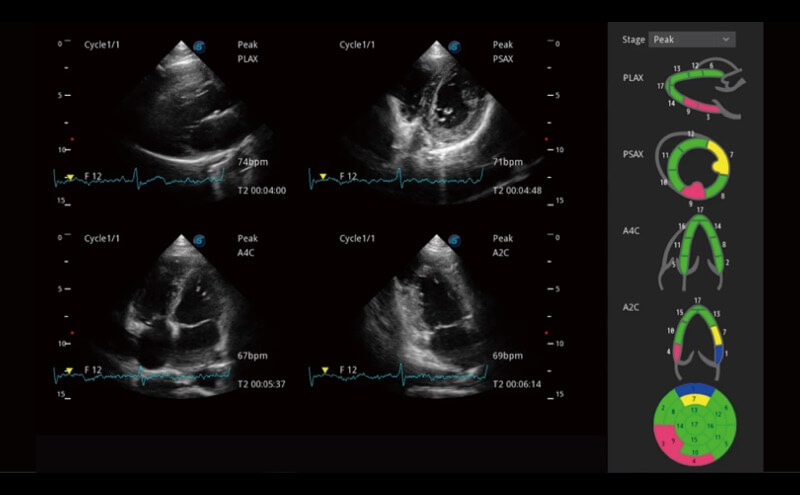

Ultraschall wird immer vielseitiger und übernimmt immer mehr klinische Aufgaben. Als Vorreiter, der Ärzten dabei hilft, mehr zu erreichen, ist ELITE mit einer umfassenden Palette fortschrittlicher Funktionen für die Allgemeine Bildgebung, Gynäkologie/Geburtshilfe, Kardiologie und mehr integriert.

Ultraschall wird immer vielseitiger und übernimmt immer mehr klinische Aufgaben. Als Vorreiter hilft ELITE den Ärzten dabei, mehr zu erreichen, indem es mit einer umfassenden Palette fortschrittlicher Funktionen ausgestattet ist, die die allgemeine Bildgebung, die Geburtshilfe/Gynäkologie, die Kardiologie und vieles mehr abdecken.